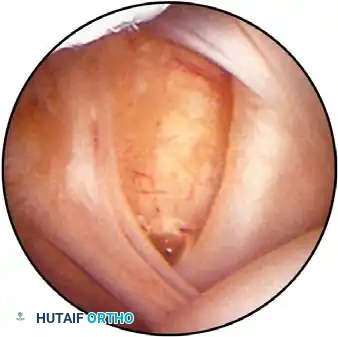

Once diagnostic evaluation is complete and hemostasis is secured, the therapeutic phase commences. Whether performing a SLAP repair, a Bankart stabilization, or a rotator cuff repair, the principles of tissue mobilization, anatomical footprint restoration, and secure biomechanical fixation remain paramount.

Modern arthroscopy relies heavily on suture anchors (biocomposite or all-suture constructs) and advanced arthroscopic knot-tying or knotless techniques. The ability to pass sutures through retracted, fibrotic tissue and secure them under appropriate tension without strangulating the microvascular supply is the hallmark of a master arthroscopist.